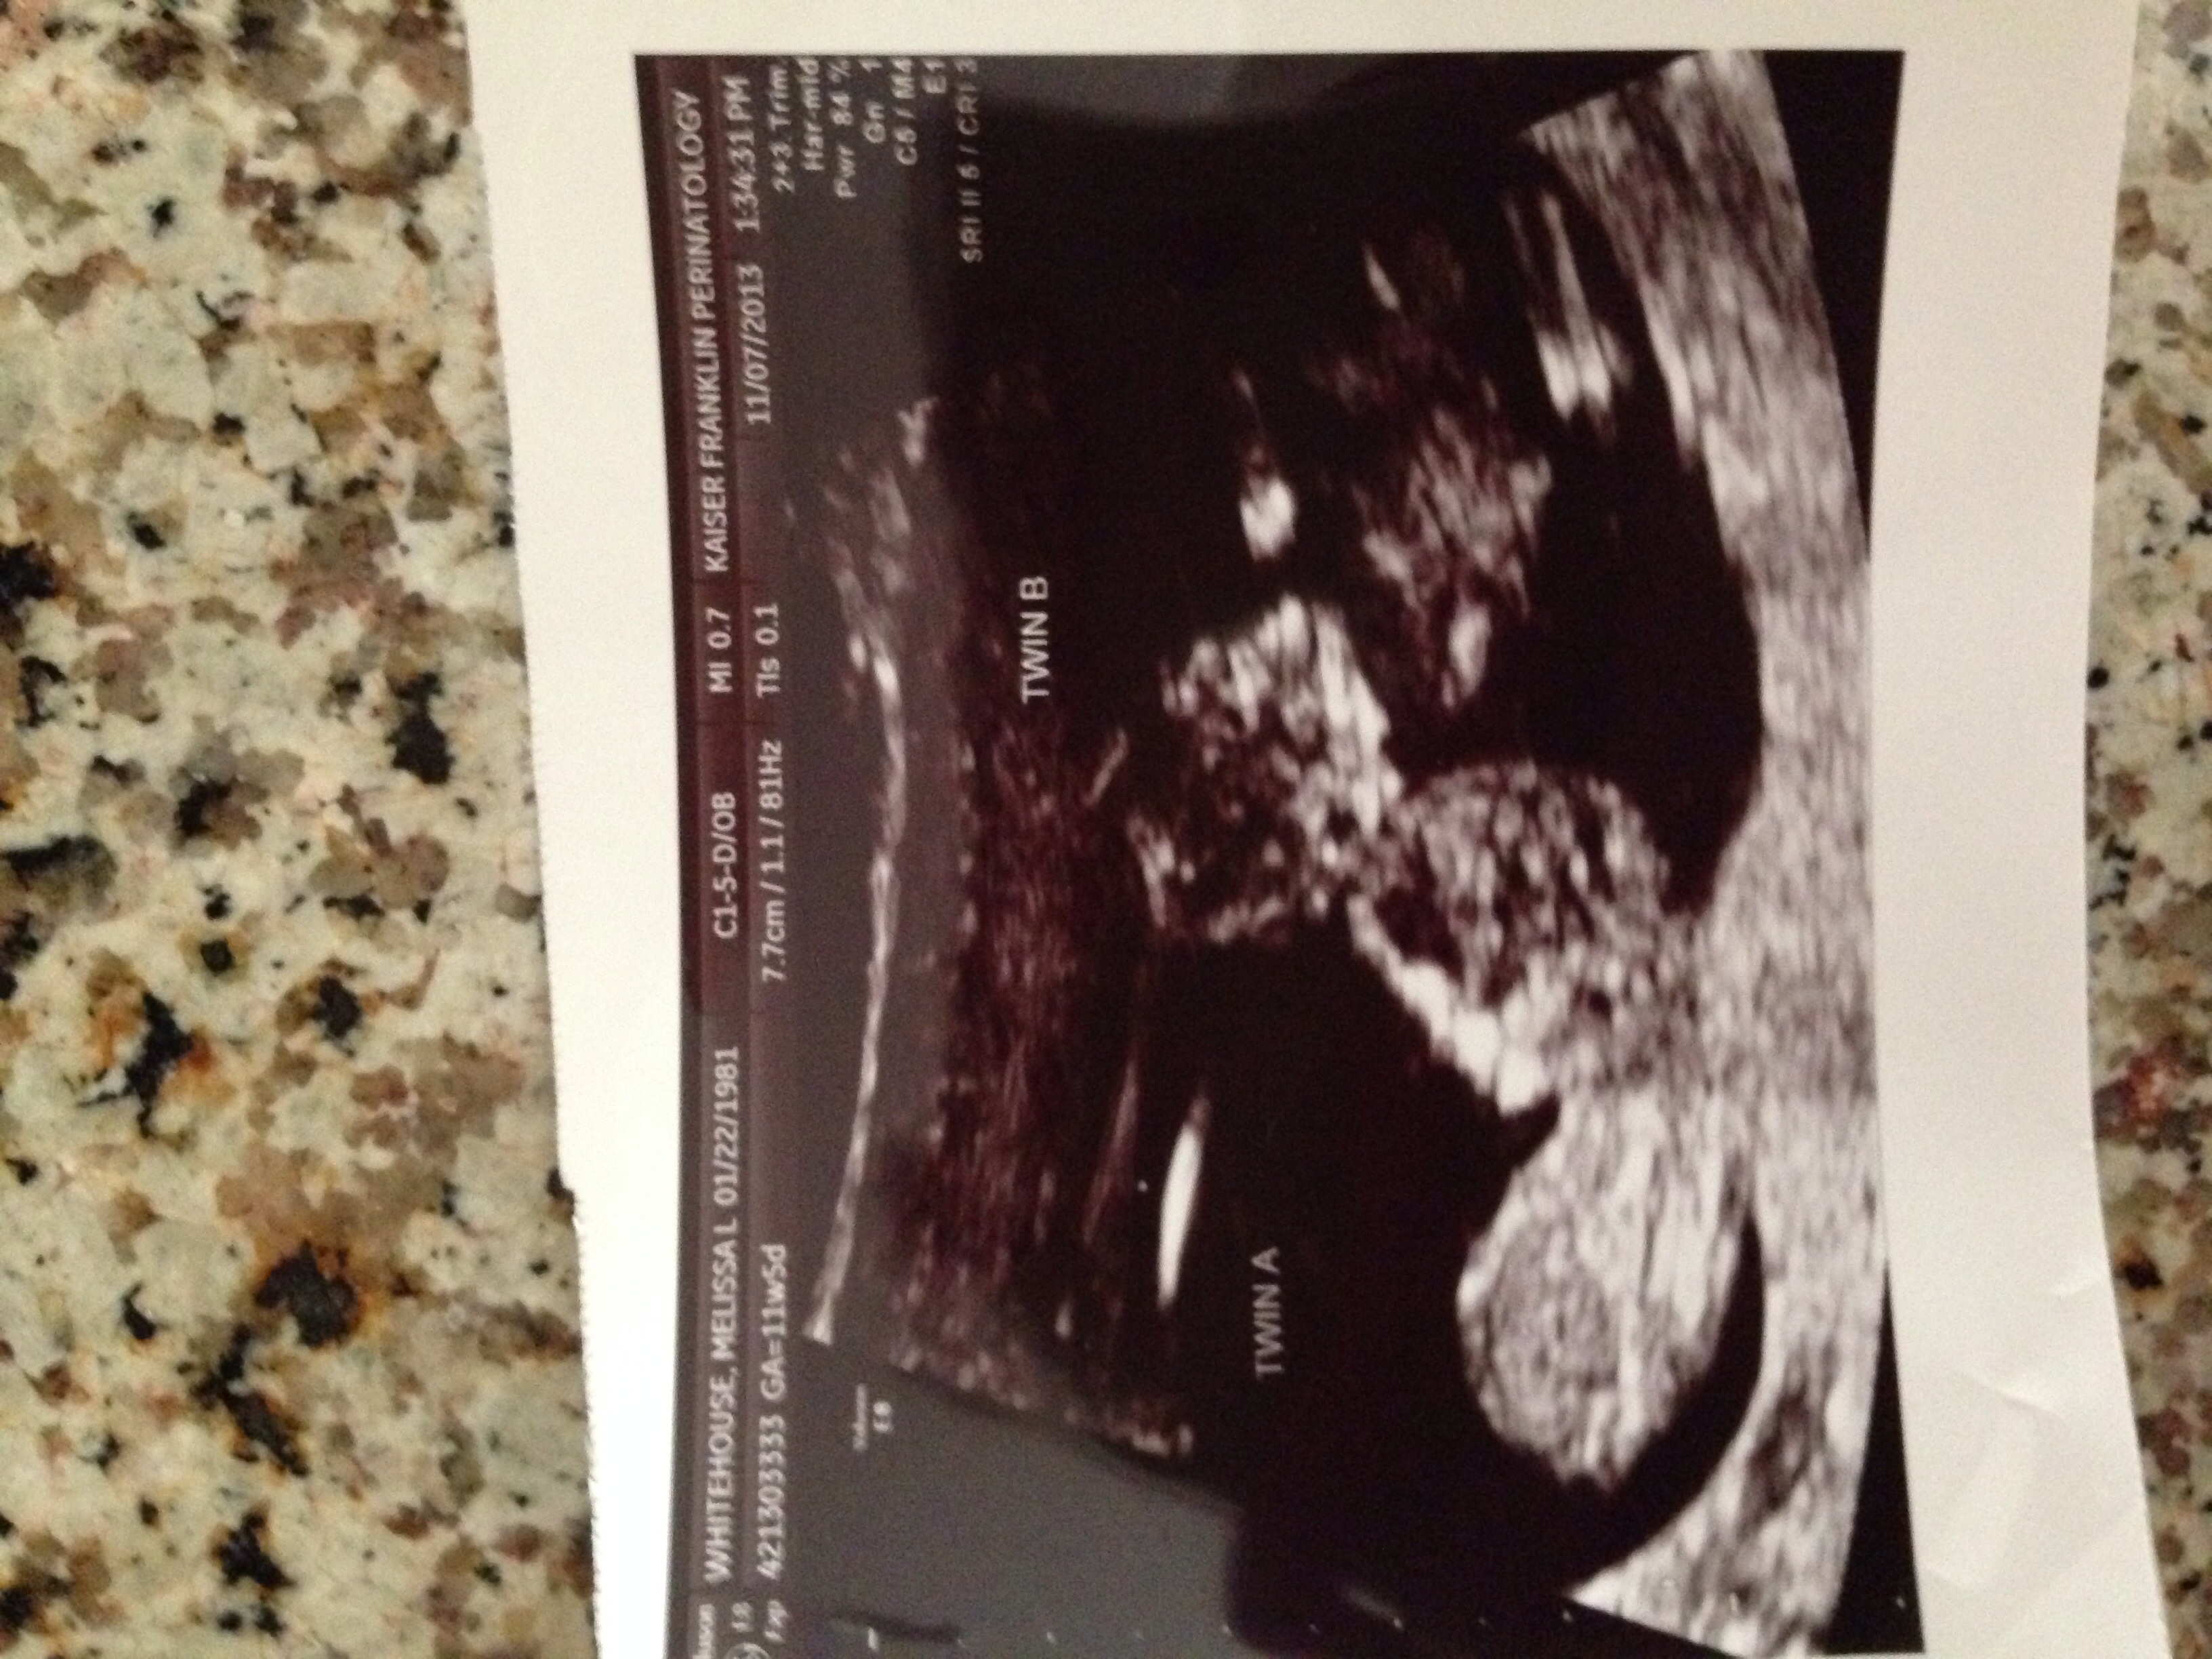

9dp5dt Beta 1 = 344!! 16dp5dt. Beta 2 = 4822 7wk u/s= 2 heartbeats!

Twin girls! 3/6/14